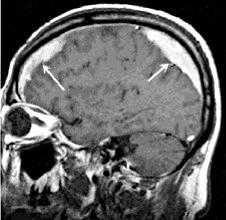

Магнитно-резонасная томография

Проявления обычно обусловлены биохимическими свойствами гемоглобина который варьируют от сроков гематомы. Наиболее чувствительной является FLAIR последовательность.

- FLAIR: гиперинтенсивный сигнал, по отношению к сигналу ЦСЖ

- T1: интенсивность сигнала варьирует от изо- до гиперинтенсивного, по отношению к сигналу от серого вещества головного мозга

- T2: сигнал гипоинтенсивный, по отношению к серому веществу

При проведении МРТ может наблюдаться пониженная контрастность зоны острой гематомы; хронические субдуральные гематомы, как правило, отличаются гиперинтенсивностью в Т2 режиме. В затруднительных случаях помогает МРТ с контрастированием. Интенсивное накопление контраста капсулой гематомы позволяет дифференцировать ее от арахноидальной кисты или субдуральной гигромы.